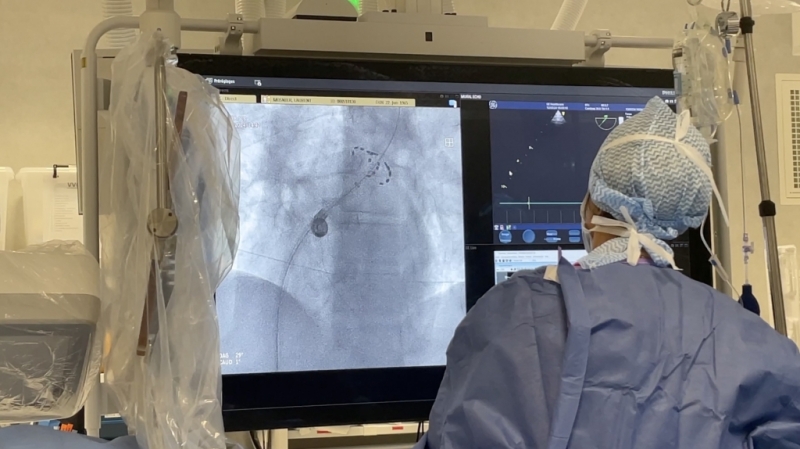

Dotée de technologies de pointe, la nouvelle salle de rythmologie permet de traiter de manière plus efficace et plus rapide les patients atteints de troubles cardiaques.

Ces nouvelles technologies existent déjà dans l'Hexagone mais le CHU de Saint-Etienne est l'un des premiers à y avoir accès dans la région Auvergne-Rhône-Alpes.

Le CHU utilise notamment une nouvelle source d'énergie : l'électroporation. Ce système élimine les foyers anormaux de manière plus sécurisée.

"C'est une énergie qui est beaucoup plus sûre que les énergies utilisées précédemment. Elle permet une plus grande sécurité dans le traitement du trouble du rythme cardiaque" indique le Professeur Da Costa, médecin cardiologue au CHU de Saint-Etienne.

Le CHU a investi 1,8 million d'euros dans cette nouvelle salle. Plusieurs patients ont déjà pu en profiter ces derniers mois.